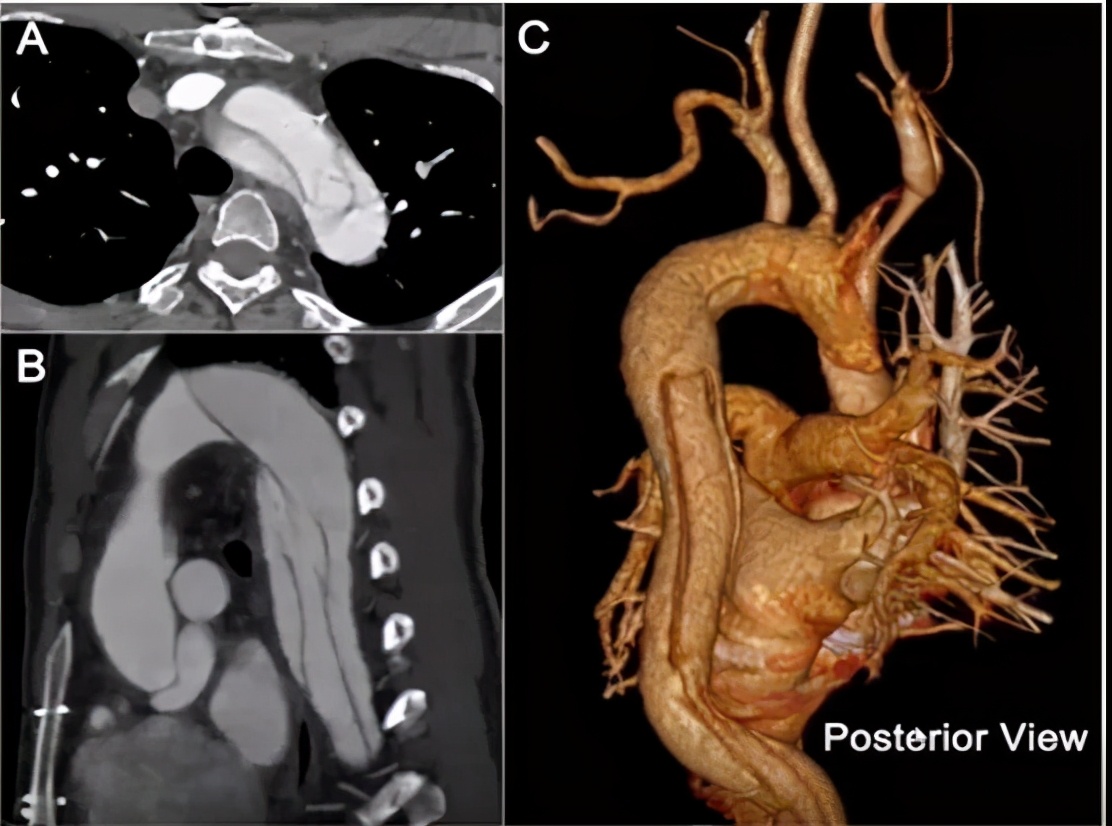

病例4(男性,33岁)

主诉:急性胸背痛3小时。

既往史:高血压、糖尿病、马凡综合征。

手术史:3年前因“升主动脉瘤+AI(重度)”行Bentall手术。

查体:无明确灌注缺血综合征。

实验室检查:无特殊。

心脏彩超:(-)。

手术方法:IA烟囱+LCCA三明治+LSA封堵+LCCA-LSA搭桥+主动脉腔内修复术。

手术步骤:左颈总动脉-左锁骨下动脉搭桥;胸降主动脉支架(Ⅱ)释放到位;无名动脉“烟囱”支架+左颈总动脉支架放置到位,不释放;近心端主动脉支架(Ⅰ)近段+无名动脉“烟囱”支架释放;升主动脉支架(Ⅰ)远端+左颈总动脉“三明治”支架释放;左锁骨下动脉起始部封堵。